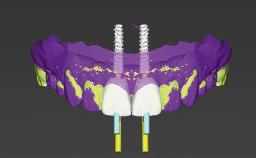

Replacement of a Mandibular Central Incisor with an Immediately Placed Monotype Zirconia Implant

In this case, immediate implant placement and an immediate provisional prosthetic reconstruction (type 1A) were performed by Stefan Röhling and Thomas Borer to reduce the treatment time and to provide the patient with a fixed implant-supported prosthetic reconstruction directly after implant placement.

| Prosthetic volume | Adequate. Space available for ideal anatomy of the restoration |

| Inter-occlusal space | Adequate. Capable to create an anatomically & functionally correct planned restoration |

| Volume and characteristics of the edentulous ridge (fixed) | Adequate. No adjunctive therapy or prosthetic soft tissue replacement will be necessary |

| Loading Protocol | Immediate |

| Implant-supported provisional restoration | Required, non-esthetic site and/or functional demands |